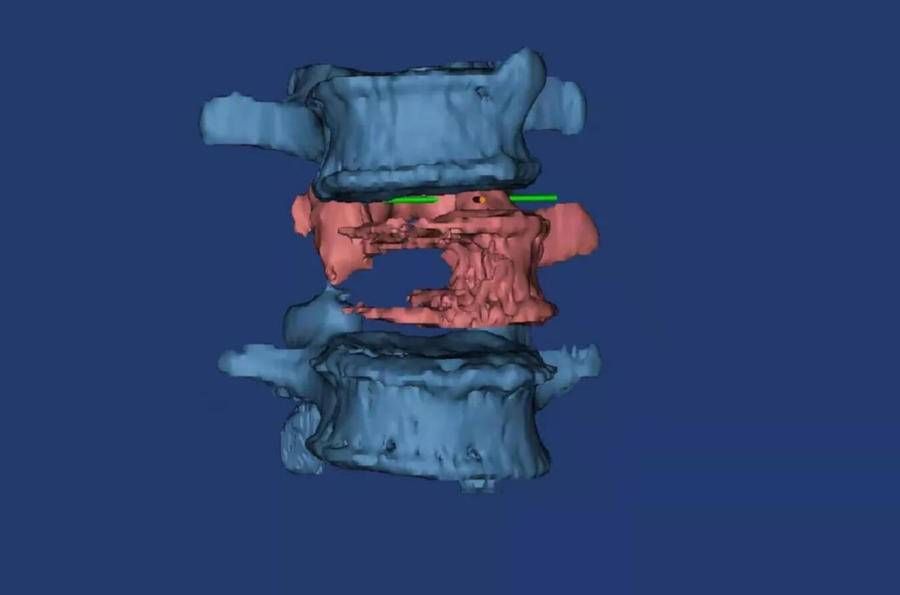

术前3D打印模型显示腰3椎体右侧半被肿瘤“吃”空了。